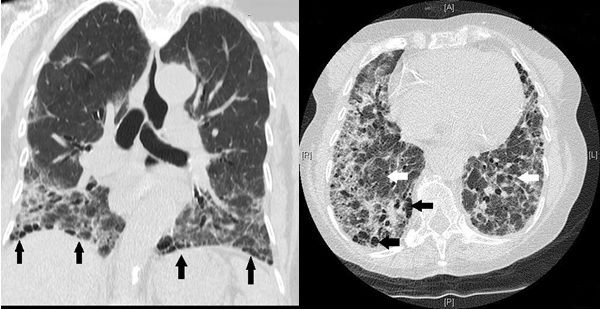

Rheumatoid arthritis (RA)–associated interstitial lung disease (RA-ILD) is an increasingly common extra-articular cause of mortality and morbidity in RA. Here, we present the case of an 82-year-old female suffering from RA-ILD. She presented with a 20-year history of RA with new-onset progressively worsening dyspnoea, pyrexia, and dry cough, which were not responsive to initial antibiotics. Moreover, she had been on long-term methotrexate, which can cause pulmonary disease. Investigations revealed raised inflammatory markers, restrictive lung patterns, and radiological features of ILD. She was treated with a tapering course of oral prednisolone and home oxygen, which provided some symptomatic improvement. Diagnosis of RA-ILD can be challenging due to several contributing factors. Optimal treatment is controversial, and corticosteroids have been widely used but with limited effects. There is evidence directed at potential therapeutic benefit from a number of newer agents, which are discussed.

Tanaka N, Kim JS, Newell JD, Brown KK, Cool CD, Meehan R, et al. Rheumatoid arthritis-related lung diseases: CT findings. Radiology. 2004 Jul;232(1):81-91. DOI: 10.1148/radiol.2321030174.

Akira M, Sakatani M, Hara H. Thin-section CT findings in rheumatoid arthritis associated lung disease: CT patterns and their courses. J Comput Assist Tomogr. 1999 Nov-Dec;23(6):941-8. DOI: 10.1097/00004728-199911000-00021.